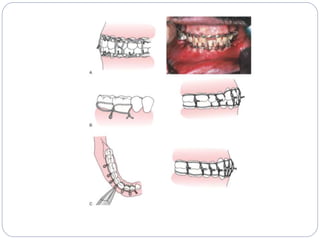

‫شکستگی‬ ‫وضعیت‬

‫شکستگی‬ ‫خط‬ ‫به‬ ‫نسبت‬ ‫عضالت‬ ‫کشش‬ ‫اساس‬ ‫بر‬

‫مطلوب‬(Favorable)

‫نامطلوب‬(Unfavorable)